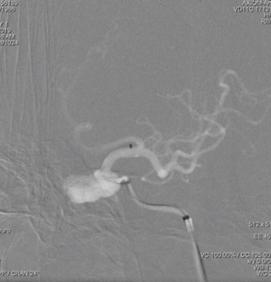

6F Navien导管超选至动脉瘤远端,微导丝引导下WILLIS®支架到位。

球囊首次扩张,支架展开,首次造影图示动脉瘤近端贴壁不良,有造影剂渗漏至动脉瘤腔内,故再次充盈球囊扩张支架近端。

再行造影见动脉瘤不显影,无造影剂渗漏,血管重建满意。